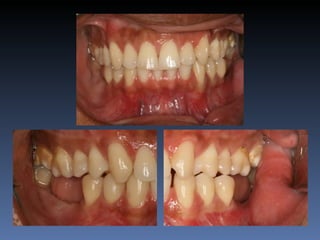

Diagnóstico: Desdentado parcial

pré-maxila.

Plano de tratamento: Reabilitação pré-maxila com

instalação de 2 implantes endo-ósseos (1.1,.2.2), para

reabilitação protética fixa.